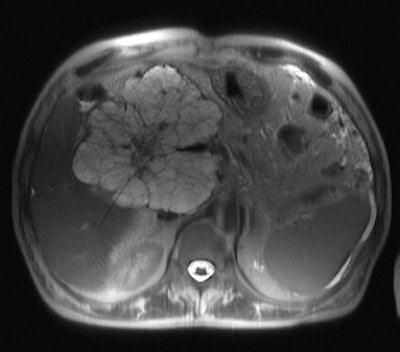

A case in point that determines management is whether pancreatic lesions are solid or cystic. A solid lesion must be resected, if possible, according to Bassi, while some cystic lesions can be followed up, as will be covered more fully by Zamboni, who will illustrate the different pathological patterns of pancreatic neoplasms, cystic and solid, their immunohistochemistry, and the possible progression from benign to malignant pancreatic tumor.

Depending on the indication, different surgical procedures for determining whether the lesion is a neoplasm or not mean different questions exist for the pathologist and the radiologist. The pathologist should know the criteria helpful for the differential diagnosis with tumor-like conditions that do not require surgery but medical therapy instead, while radiologists should know the diagnostic imaging signs for differential diagnoses in patients with a mass in the pancreas, Manfredi commented.